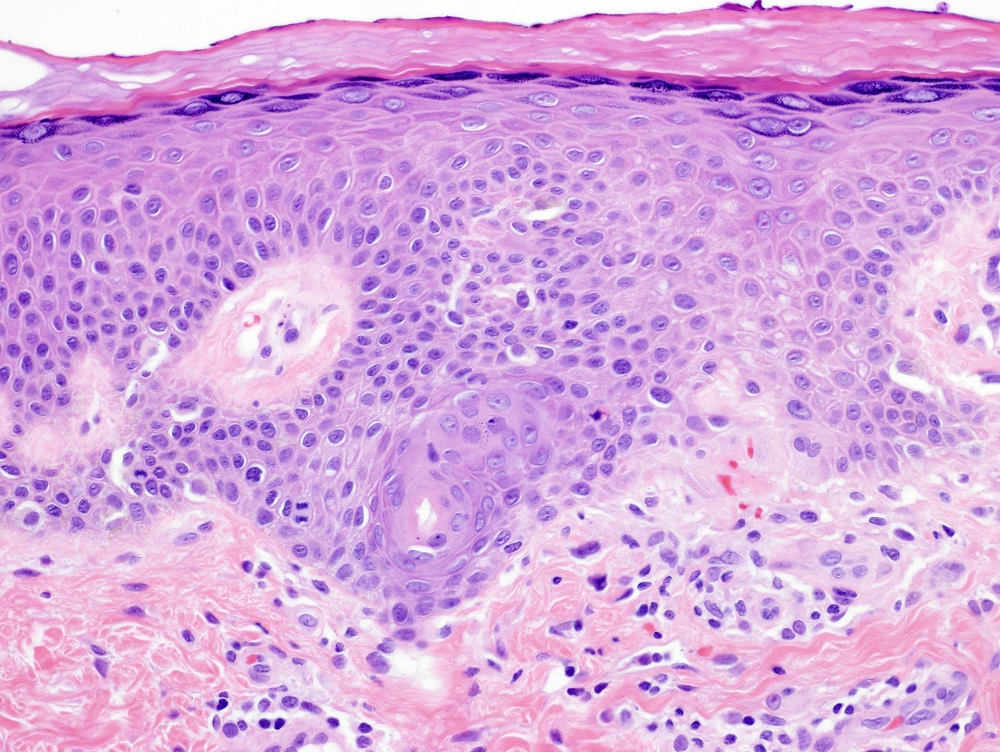

Secções de uma lesão de miliária rubra coradas com hematoxilina e eosina demonstram espongiose de um ducto sudoríparo intraepidérmico, às vezes formando uma vesícula espongiótica, com exocitose linfocítica e um infiltrado perivascular superficial de linfócitos e neutrófilos.

[Figure caption and citation for the preceding image starts]: Fotomicrografia de miliária rubra mostrando espongiose acrossiríngea intraepidérmica e inflamação crônica subjacente (H&Ex400)Do acervo de Brian L. Swick, usado com permissão [Citation ends].